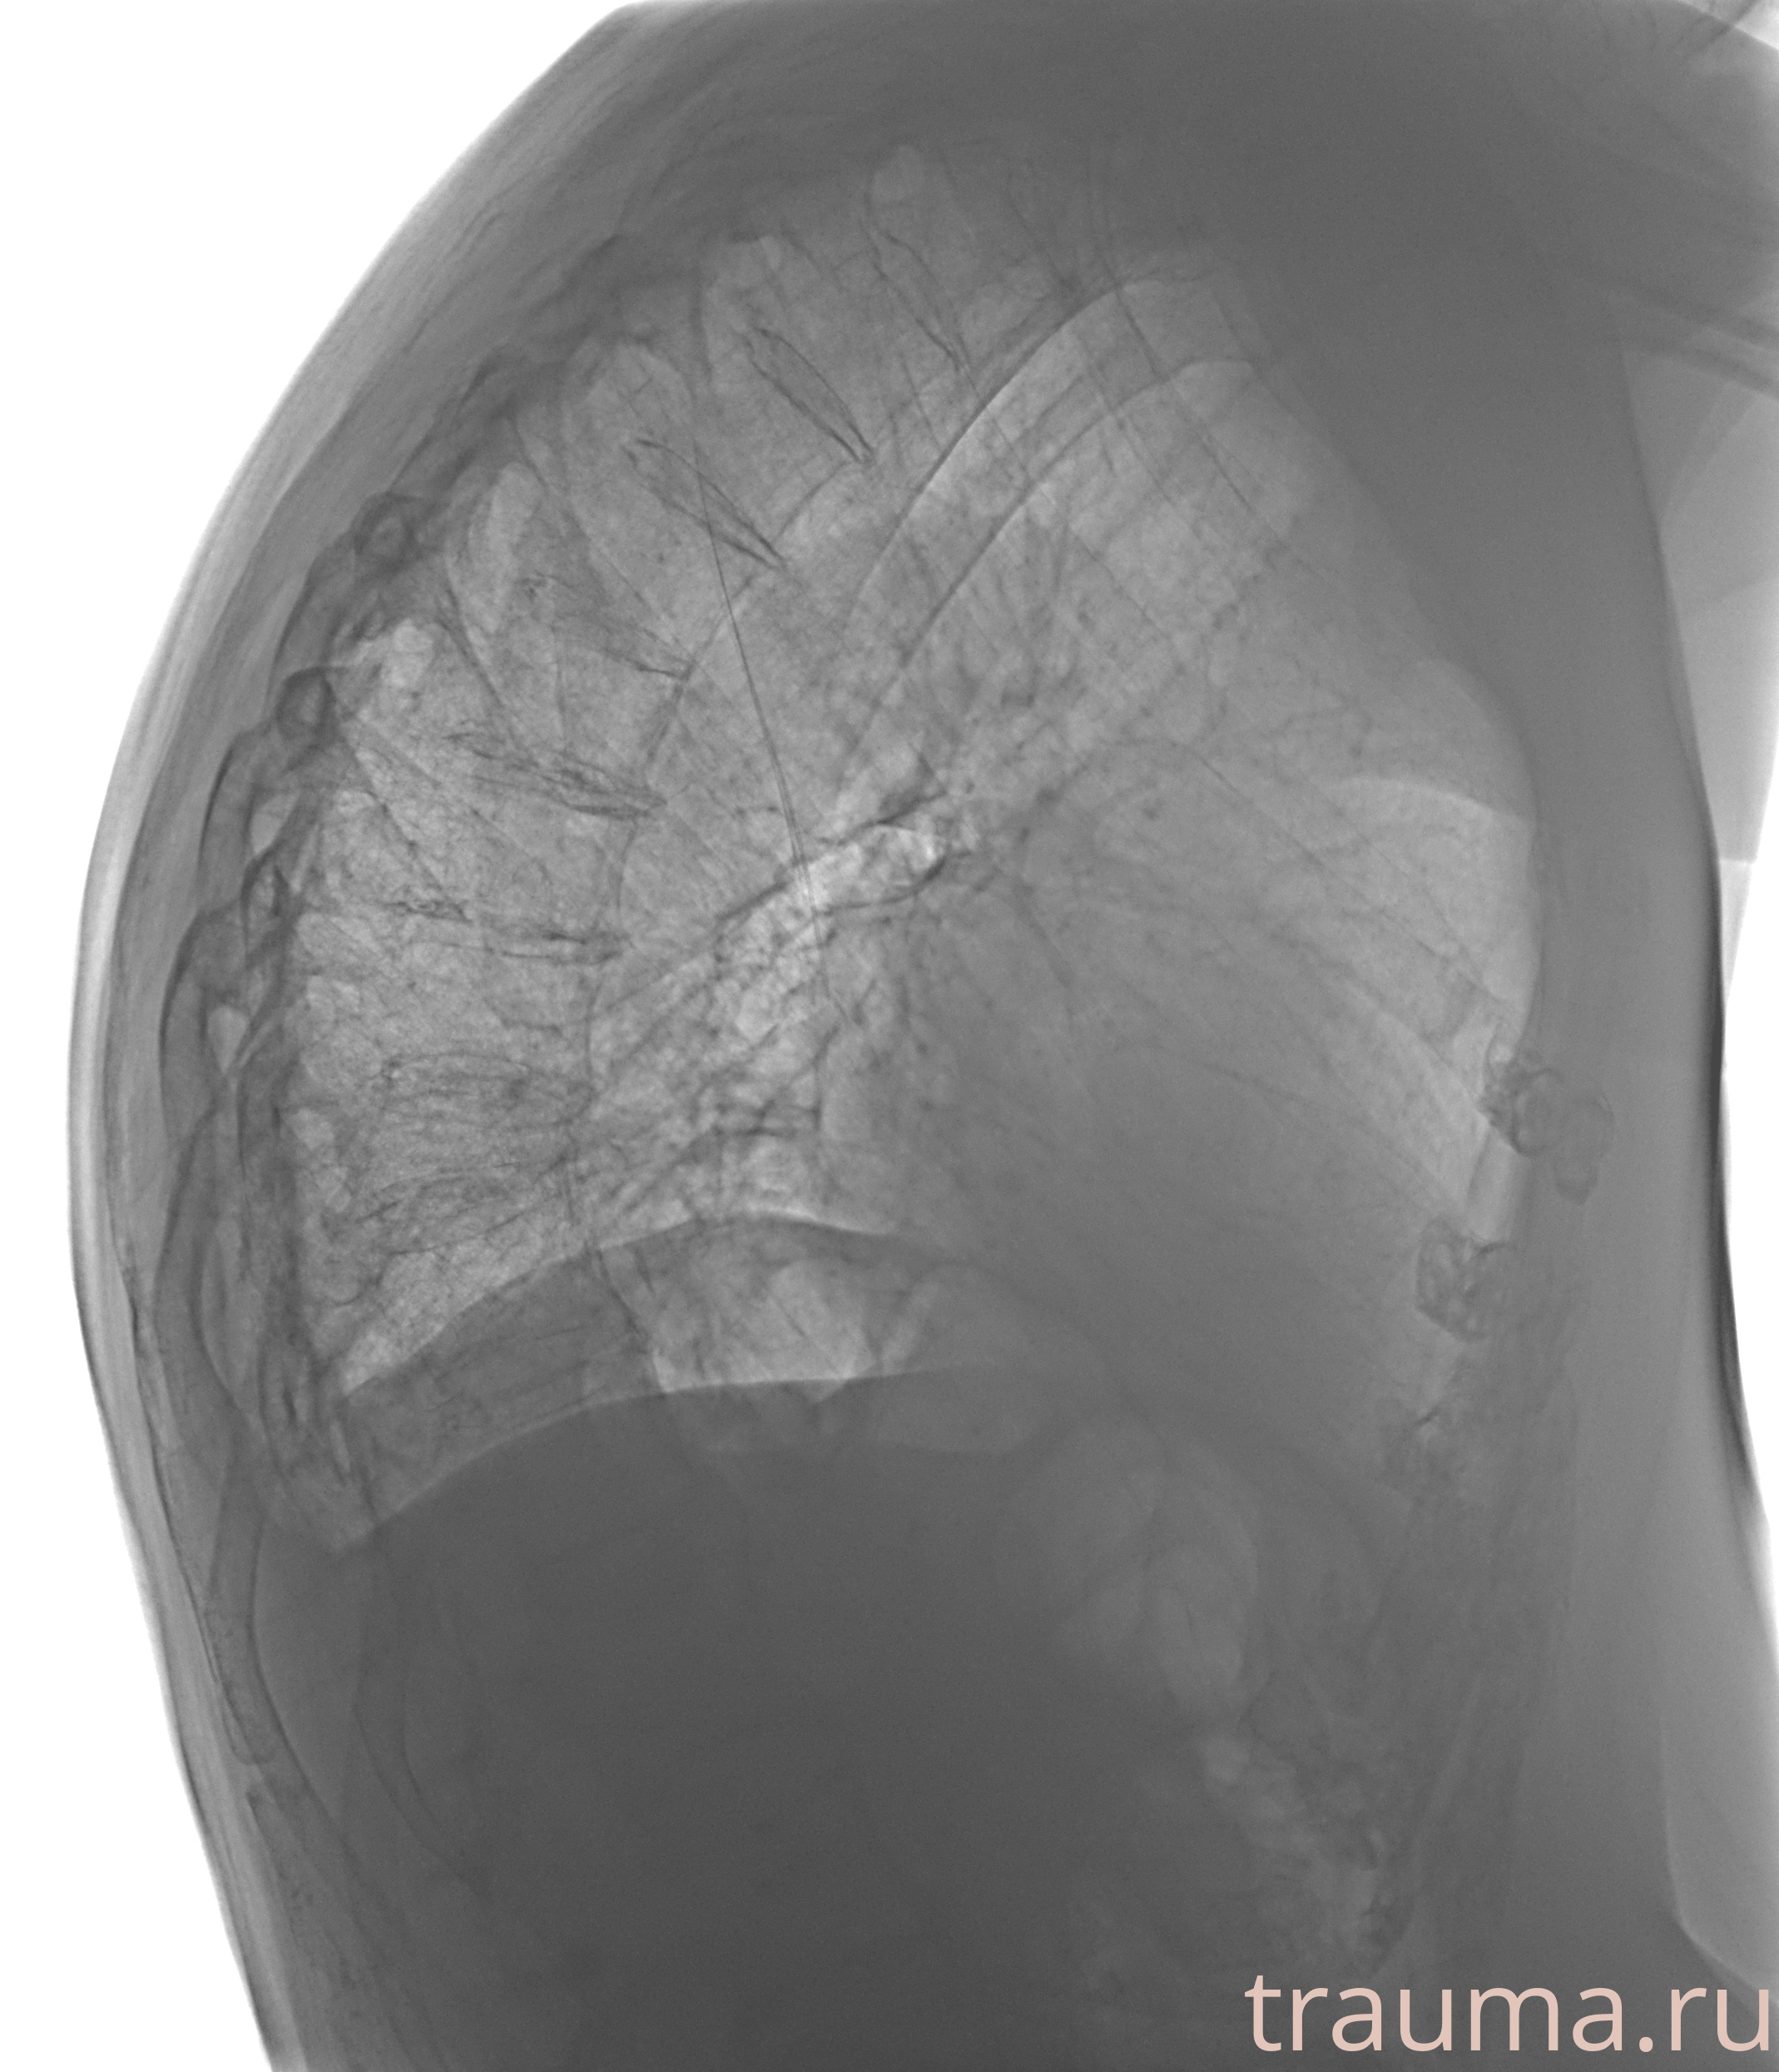

Рентгенограммы

Рентген на дому: по вашему адресу приезжает врач-рентгенолог, травматолог-ортопед с мобильным рентгеновским аппаратом, проводит диагностику травмы или заболевания, делает необходимые рентгенограммы, дает рекомендации по дальнейшему лечению. Получить качественные снимки в домашних условиях возможно благодаря уникальной методике, разработанной МосРентген Центром для института  Склифосовского